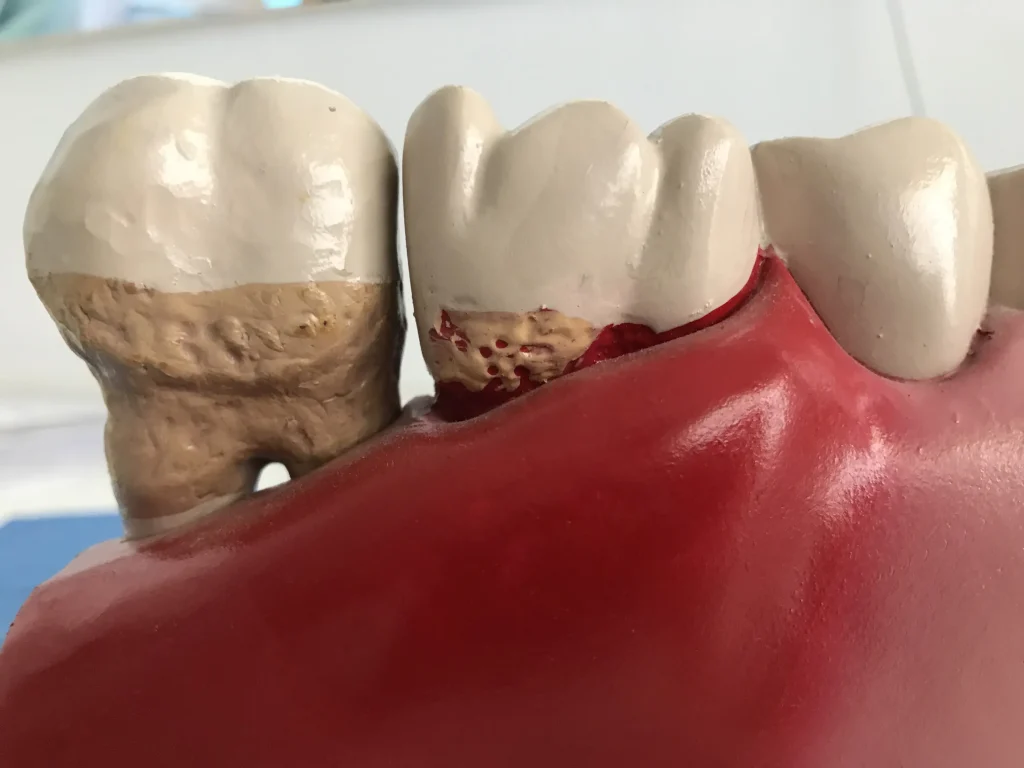

• REGENERACIÓN E INGERTO DE ENCÍA

• TRATAMIENTOS PERIODONTALES SIMPLES Y COMPLEJOS